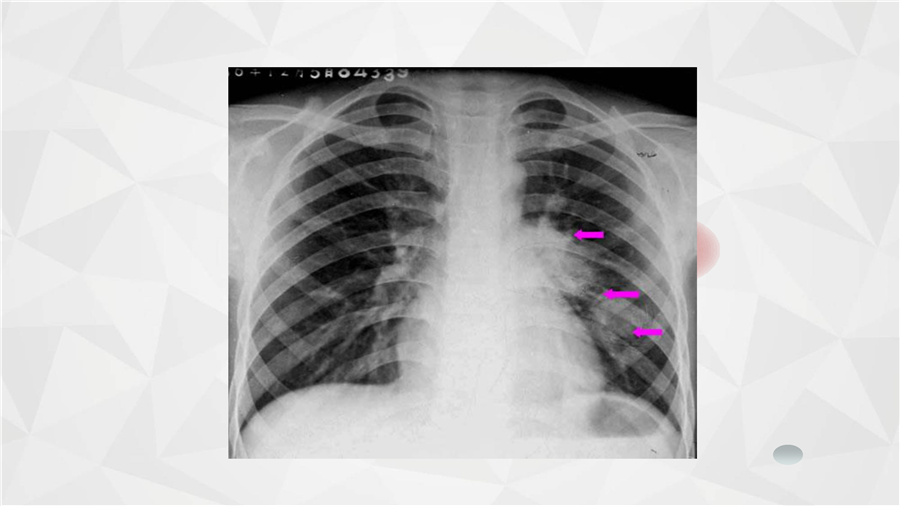

呼吸系统三